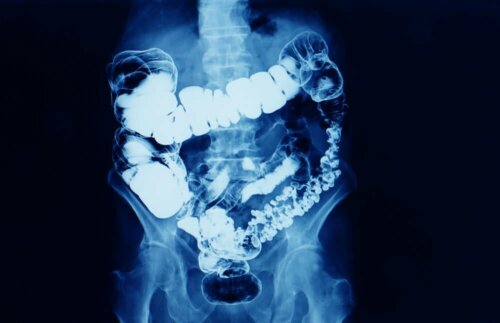

Was ist Verstopfung

Im Allgemeinen spricht man von Verstopfung, wenn die Frequenz des Stuhlgangs unter dreimal pro Woche liegt. Der Stuhl ist hart, die Entleerung erfolgt nur durch starkes Pressen und es sind oft auch Schmerzen vorhanden.